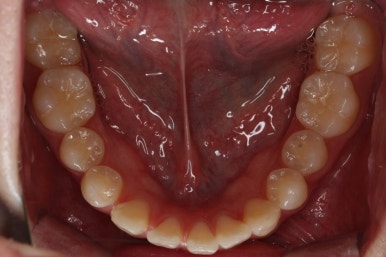

부산교정 키다리아저씨치과에 처음 내원하셨을 때의 입안 모습입니다.

윗니가 삐뚤어져 있고, 아래앞니 사이에는 틈이 듬성듬성 보입니다.

아랫니를 살펴보면 화살표 표시를 해둔 송곳니~송곳니 사이에 치아가 1개 모자랍니다. 원래는 4개의 앞니가 있어야 하는데, 3개 밖에 없었습니다. 이런 결손치아의 경우는 다음과 같은 문제가 생깁니다.

결손치아 부위에 틈이 생깁니다.

결손치아 주위 치아들이 제대로 서있지 못하고 기울어지게 됩니다.

위-아래 짝이 맞지 않아 중앙선이라든지 교합에 문제가 생깁니다.

이번의 경우 앞니가 하나 없는 경우여서 위-아래 앞니가 앞뒤로 간격이 멀어지게 됩니다.